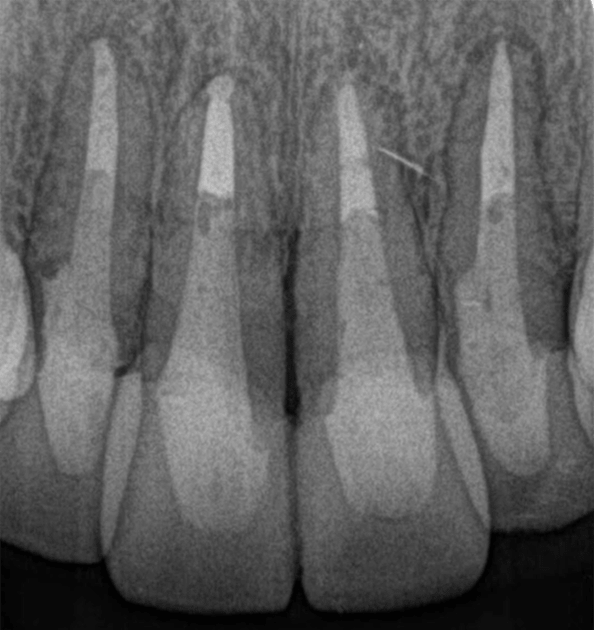

症例5【50代男性】前歯4本の根尖病巣

治療前

治療後(24ヶ月後)